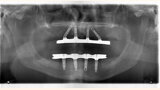

Fig. 11. Prótesis híbrida inmediata con 10 años de evolución y Rx Control a los 10 años.